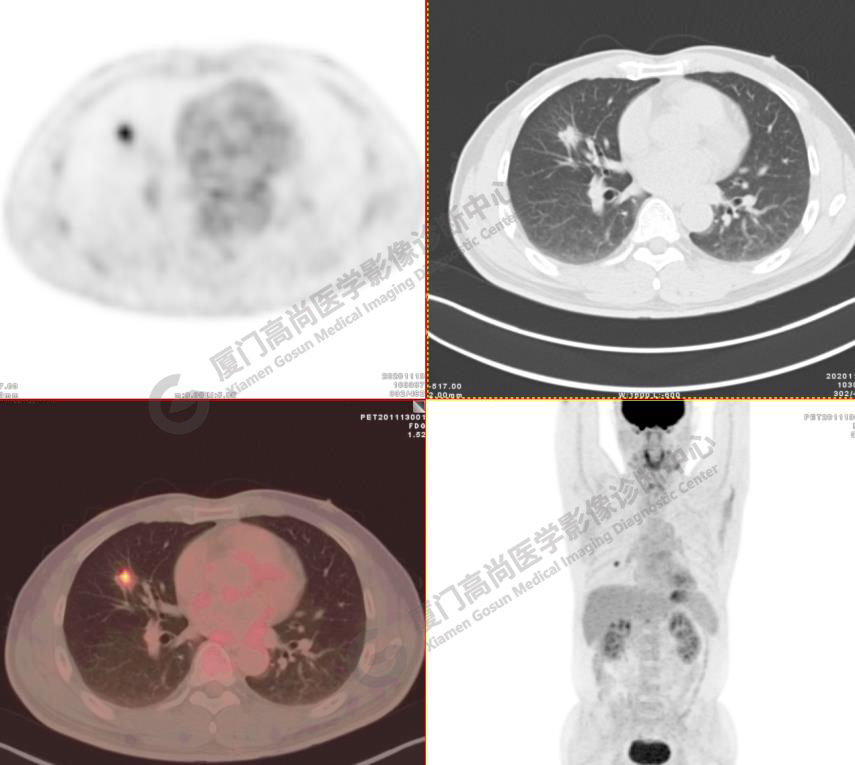

病例1:某男士,52歲,2020年11月體檢,CT發(fā)現(xiàn)右肺中葉結(jié)節(jié)影,查血腫瘤標(biāo)記物正常。

右肺中葉見一混雜密度磨玻璃結(jié)節(jié),大小約1.8x1.5cm,密度不均勻,以實(shí)性密度為主,邊緣可見分葉、毛刺,水平裂牽拉凹陷,F(xiàn)DG攝取增高,SUVmax4.7,肺門、縱隔未見FDG高攝取淋巴結(jié), 未見遠(yuǎn)處轉(zhuǎn)移征象。

影像診斷:右肺中葉浸潤性腺癌。(TNM分期 T1bN0M0 ⅠA2期)

病理診斷:浸潤性腺癌